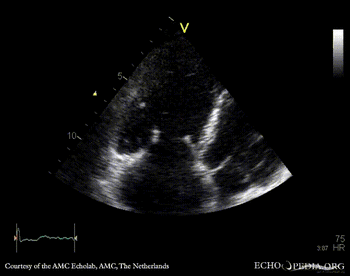

E00346.gif E00347.gif

PLAX: enlarged right ventricle in patient with carcinoid PSAX: enlarged right ventricle in patient with carcinoid, diastolic flattening of IAS